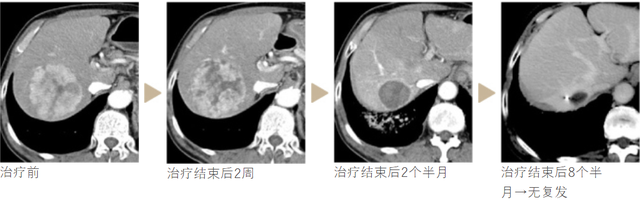

典型案例治疗进度图: